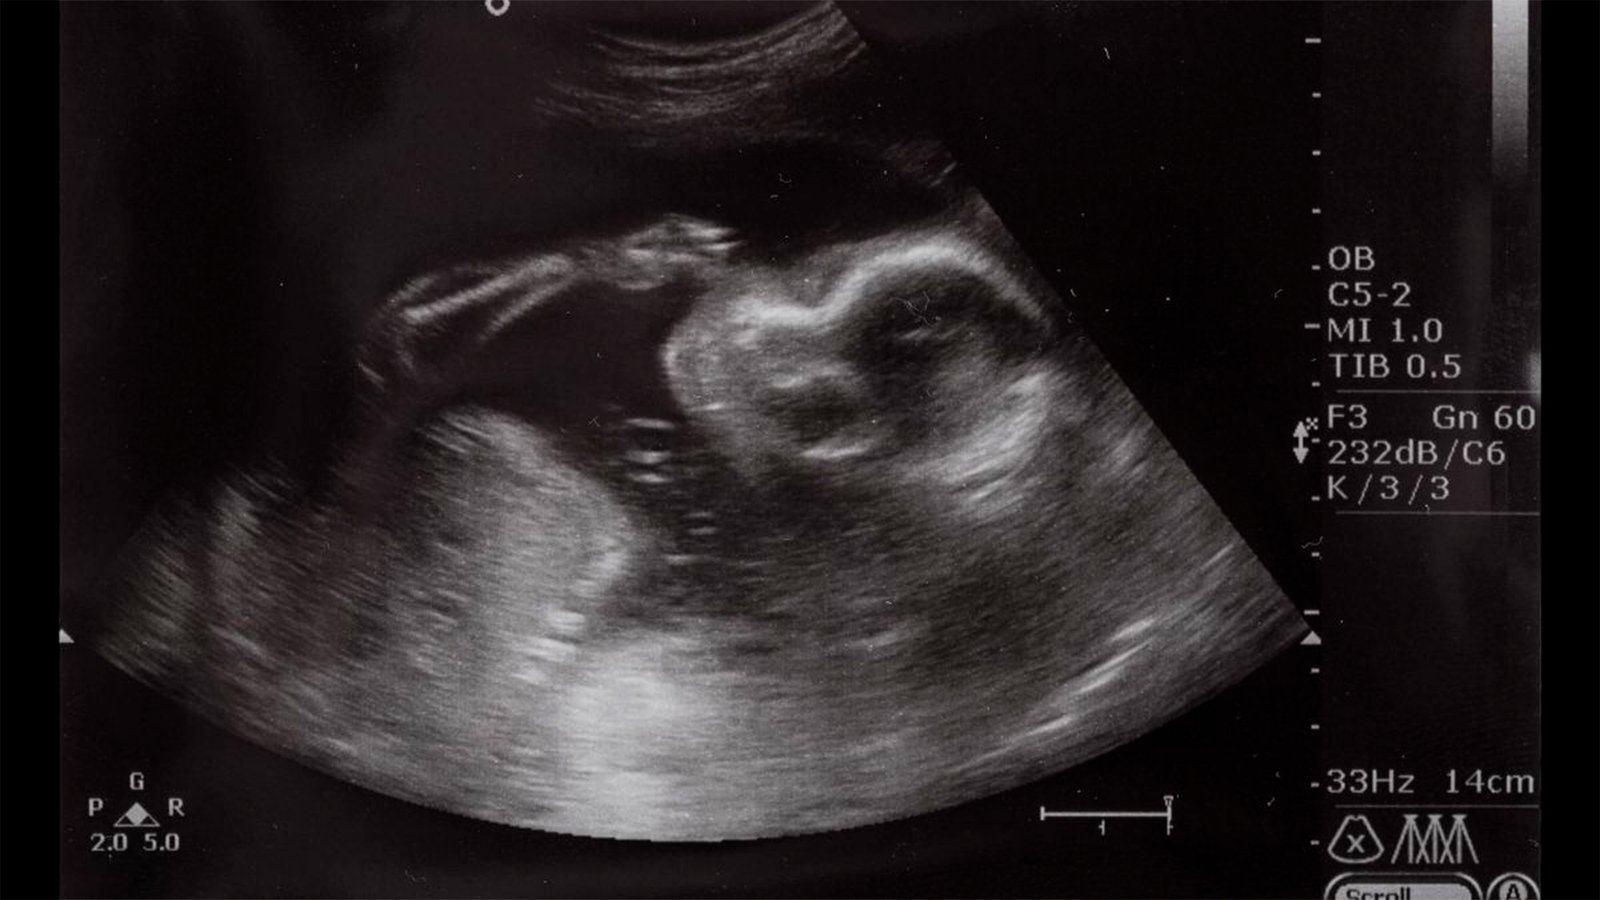

Gerar – 6º mês

A Série Gerar, produzida pela TV GAZETA, foi composta por nove episódios dentro do programa Mulheres, com o Dr Cláudio Basbaum abordando as mudanças físicas e emocionais da gestante em cada mês da gestação.